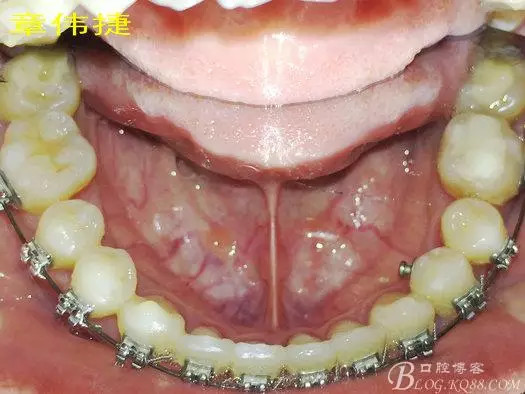

矯治八個(gè)月術(shù)中資料:

經(jīng)過(guò)8個(gè)月的治療,患者的間隙已完全關(guān)閉,患者非常滿(mǎn)意,后期進(jìn)入精細(xì)調(diào)整階段,建議做舌體修整術(shù),防止復(fù)發(fā)。